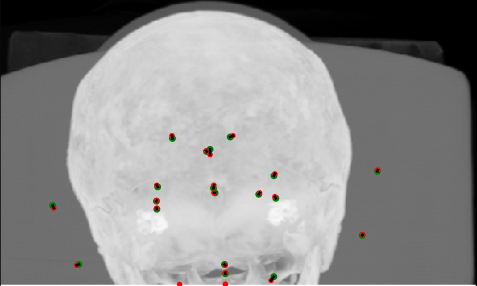

Summary metrics are shown in Table 1 for landmark localisation errors (or disagreements), and some visual results are shown for the FCN in Figures 4 and 5. The summary metrics show that the FCN outperforms the decision forest methods. The anomalous metric is the mean max error, in other words, the mean size of the “worst detected landmark in a scan”. This does not appear to improve in the second pass — if anything, the worst error worsens— and the Pass 0 decision forest with HOG features is the best performer. We propose that this occurs because landmarks with atypical appearance (e.g. see the calcified pineal gland example in Figure 5) are best located by use of spatial context rather than local appearance, hence the efficacy of low resolution HOG features which are aggregated over regions and thus are relatively insensitive to precise changes.

Figure 4: Coronal, sagittal and axial maximum intensity projections (MIPs) of results for a good case (top) and a poor case (bottom). Green dots = ground truth (observer A), red dots = detected (proposed FCN), and black lines connect corresponding pairs.